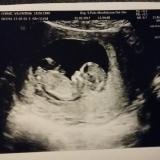

AnonimoInattivociao a tutte, prima visita ufficiale fatta e anchel’inserimento in ospedale. Tutto Ok, mi hanno ridatato la gravida cioè sarei di 13 settimane invece che 12. É molto grande 6 cm e non smetteva di muoversi…al punto che la ecografia è stata lunghissima perche non riuscivano a misurarlo…alla fine mi hanno fatto anche una 3D

dopo tornata al lavoro mi è venuta un colpo, vado in bagno e avevo delle perdite che adesso sono sparite ma secondo me hanno pressato tanto (ange se non mi hanno fatto la TVG) le ho chiamato e hanno detto se spariscono non è niente soltanto che è stato sollecitato troppo….(speriamo bene

)